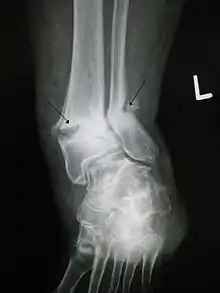

Le mécanisme de l'ostéogenèse n'est pas clair. La thérapie PEMF revendique un certain avantage dans le traitement des fractures, mais avec des preuves issues d'essais randomisés « insuffisantes pour conclure à un bénéfice de la stimulation de la croissance osseuse » dans la pratique clinique actuelle du traitement des pseudarthroses et fractures aiguës[1]. Une revue systématique et méta-analyse récente suggèrent néanmoins que « PEMF ou LIPUS peuvent être bénéfiques dans le traitement des fractures aiguës (subissant un traitement non opératoire et les fractures aiguës du membre supérieur) en ce qui concerne le temps de consolidation radiologique et clinique »[1]. Une stimulation de la croissance osseuse PEMF ou LIPUS accélère aussi la consolidation de fractures diaphysaires aiguës[1].